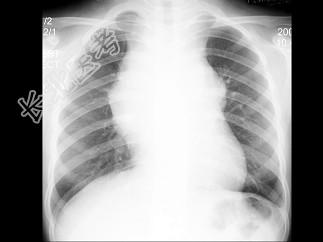

- 单项选择题女,13岁, 发热、乏力数天,X线检查如图, 最可能的诊断是 ( )

A、胸腺瘤

B、淋巴瘤

C、畸胎瘤

D、间皮囊肿

E、神经源性肿瘤